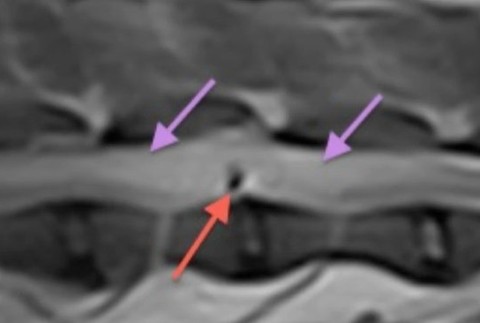

Psy behali vonku na oplotenom pozemku, keď prišla rodina domov, jednu sučku našla postrelenú. "Dávali sme nový plot. Oni nemali šancu sa dostať zo záhrady von," skonštatovala Tatiana, majiteľka psa. 6-ročná Lilly ležala v kaluži krvi a už sa nedokázala ani pohnúť. Pani Tatiana vyhľadala okamžite veterinára. "Tam jej urobili snímok a povedali nám, že je to zo vzduchovky strieľané a strela uviazla v chrbtici," povedala Tatiana.

Strela spôsobila to, že sučka kríženca zostala ochrnutá. Prognózy boli zlé, ale rodina vyhľadala ešte ďalších odborníkov. "Nedá sa prijať taká informácia hneď, tak sme išli na druhý deň do Trenčína a nám potvrdili, že skutočne bude najlepšie keď bude vykonaná eutanázia," vyjadrila sa Tatiana.